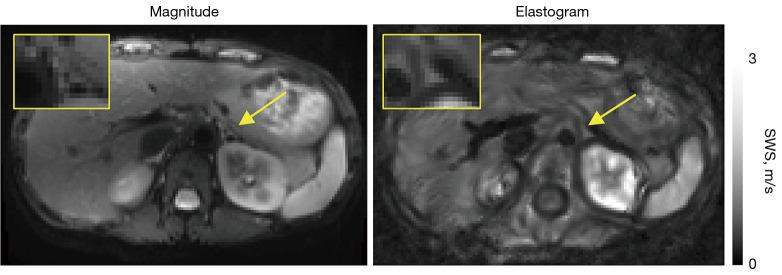

Establishment of multifrequency magnetic resonance elastography for adrenal gland imaging: feasibility and reproducibility for assessing stiffness and fluidity in the healthy adrenal gland.

The adrenal glands are small endocrine organs located in the abdominal cavity, playing a critical role in hormone production. However, they have not been studied using magnetic resonance elastography (MRE), a technique known for its sensitivity to viscoelastic differences in various abdominal organs. While MRE has been successfully applied to assess tissue stiffness in larger organs, its application to the adrenal glands remains unexplored. The purpose of this study is to establish multifrequency MRE for the non-invasive quantification of healthy adrenal viscoelasticity, with the goal of providing reference values that could be used to assess adrenal masses in future research.

In this prospective cross-sectional study, conducted from December 2020 to November 2021 at a tertiary care academic center, we analyzed the adrenal glands of 15 healthy outpatient participants, who were enrolled through convenience sampling, using multifrequency MRE at 3 T. Tomoelastography post-processing was applied at frequencies of 30, 40, 50 and 60 Hz using shear wave speed (SWS) in m/s as a surrogate for stiffness and loss angle of the complex shear modulus in rad for fluidity. Statistical analysis included the coefficient of repeatability (CR) to assess repeatability in a subgroup of twelve participants, intraclass correlation coefficient (ICC) to evaluate interobserver variability between analyses from two independent observers, and the two-tailed Wilcoxon test to evaluate lateral and sex differences as well as the relative increase in sharpness of stiffness maps after applying motion correction. Additionally, correlation analyses were performed to examine the relationship between loss angle and body mass index (BMI).

Multifrequency MRE was 100% feasible. Total median SWS and loss angle with their interquartile range (IQR) were 1.31 (1.24-1.33) m/s and 0.84 (0.79-0.91) rad with very good repeatability (CR =0.05/ICC =0.89) and (CR =0.12/ICC =0.73), respectively. Motion correction resulted in a relative increase in SWS sharpness of 12%±12% (P=0.04). Loss angle was negatively correlated with BMI (r=-0.55; P=0.04). No lateral or sex differences were observed.

Multifrequency MRE provides direct analysis of viscoelasticity of the adrenal glands on high-resolution elastograms with an excellent repeatability, providing direct analysis of small organs such as the adrenal glands directly on the elastograms. Our study provides first reference values of viscoelasticity of the adrenal gland.